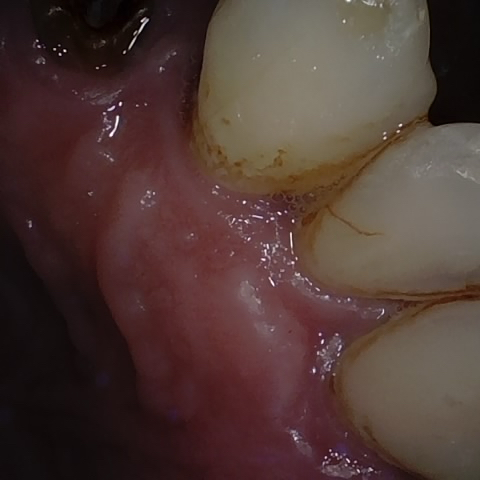

Annotated as "Good"